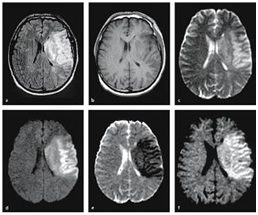

Nghiên cứu ứng dụng chụp cộng hưởng từ xung khuếch tán và tưới máu trong chẩn đoán sớm và tiên lượng nhồi máu não cấp (23/08/2016)

Năm 2015, nhóm nghiên cứu do GS.TS. Phạm Minh Thông, Bệnh viện Bạch Mai, Bộ Y tế đã tiến hành nghiên cứu đề tài: “Nghiên cứu ứng dụng chụp cộng hưởng từ xung khuếch tán và tưới máu trong chẩn đoán sớm và tiên lượng nhồi máu não cấp” với các nội dung nghiên cứu chính bao gồm Nghiên cứu đặc điểm hình ảnh cộng hưởng (MRI) từ nhồi máu não như thời gian từ khi khởi phát đến khi được chụp MRI, vị trí nhồi máu não, vị trí tắc mạch máu, số lượng thương tổn, thể tích tổn thương nhồi máu não. Vai trò của cộng hưởng từ trong chẩn đoán và tiên lượng nhồi máu não và giá trị của MRI với các chuỗi xung khác nhau. Nghiên cứu vai trò phố hợp các chuỗi xung trong tiên lượng nhồi máu não của cộng hưởng từ. Nghiên cứu hình ảnh MRI và biến chứng chảy máu nội sọ sớm. Các kết quả nghiên cứu đã được công bố trên tạp chí Điện quang Việt Nam và tạp chí Y học thực hành.